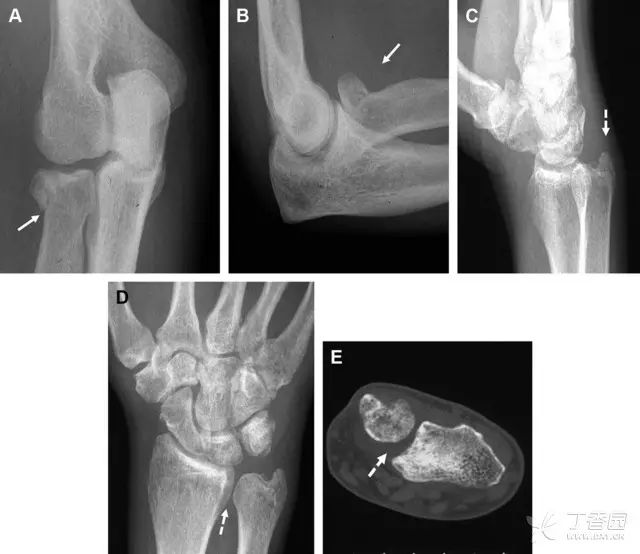

多发生于摔倒时,手掌撑地,受到轴向、外翻应力所致。常规的前后位片容易漏诊,常需加拍内斜位、外斜位、桡骨头-肱骨小头位片。后脂肪垫可见(位于鹰嘴窝内,一般不可见)和/或前脂肪垫抬高常提示骨性损伤。

图 2 桡骨头骨折。前后位(A)和侧位(B)片示后脂肪垫抬高(黑色箭头),前脂肪垫抬高(白色箭头),呈「帆船征」,其它表现正常;外斜位(C)和桡骨头–肱骨小头位(D)示桡骨头关节内骨折线(虚线黑箭头)累及桡骨颈(虚线白箭头)

肩胛骨几何形状复杂,受到邻近其它骨性结重叠阻挡,且肩胛骨骨折少见,因此容易漏诊。当存在解剖变异时,诊断更为困难。

图 3 肩胛骨骨折正侧位片:由于骨块的叠加,(A)前后位片示「V」形高密度影(*),肩胛颈下方可见骨皮质碎片(箭头);(B)侧位片示骨皮质中断,骨折段移位,但由于肱骨的重叠遮挡,决断往往比较困难

Essex-Lopresti 损伤是桡骨头骨折伴有下尺桡关节脱位,导致骨间膜损伤,桡骨短缩。此种损伤,桡骨头骨折的诊断往往是明确的,容易忽视的是下尺桡关节脱位,特别是早期,下尺桡关节的症状不明显,X 线表示也不明显。

图 8 Essex-Lopresti 损伤。前后位(A)和侧位(B)示桡骨头关节内骨折(白色实线箭头);(C~E)伤后 1 个月复诊,患者诉腕关节疼痛,X 线(C,D)发现下尺桡关节脱位,(E)CT 进一步证实损伤的存在